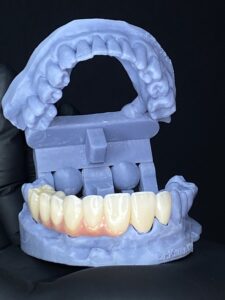

Desde prótesis parciales hasta prótesis completas, tenemos la solución ideal para recuperar tanto la funcionalidad como la estética de tu boca.

Usamos materiales resistentes y estéticos para garantizar que tu prótesis se vea y funcione como dientes naturales.

Ofrecemos prótesis dentales fijas y removibles diseñadas específicamente para ti, asegurando un ajuste perfecto y una sonrisa natural.

Prótesis dentales reemplazan dientes faltantes, pueden ser parciales o completas.

Cuando estés en presencia de ausencias dentarias, y estas pueden ser reemplazadas de distintas maneras entre ellas tenemos el grupo de las fijas y el grupo de las removibles, así como también realizamos prótesis de mayor envergadura como coronas sobre implante y prótesis hibrida.